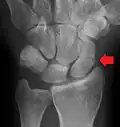

An X-ray showing a fracture through the waist of the scaphoid

Fracture of the tubercle of the scaphoid bone of the wrist